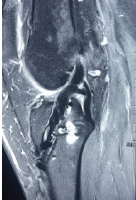

All patients had undergone a thorough clinical assessment. DFO was diagnosed based on at least one clinical feature, such as a positive probe-to-bone test, visible bone at the ulcer base, or at least one of the following supportive radiographic features on a plain radiograph: Periosteal reaction, loss of trabecular architecture, endosteal scalloping, bone destruction, or sequestered bone [8]. To confirm OM in patients with a doubtful diagnosis on plain X-ray, magnetic resonance imaging (MRI) was performed (Fig. 2). The presence of periosteal reaction, sequestrum, and a characteristic alteration in bone marrow signal intensity on MRI led to the diagnosis of OM [9]. ESR, CRP, and PCT levels were compared in the osteomyelitic and non-osteomyelitic groups at 0, 15, and 30 days of treatment.